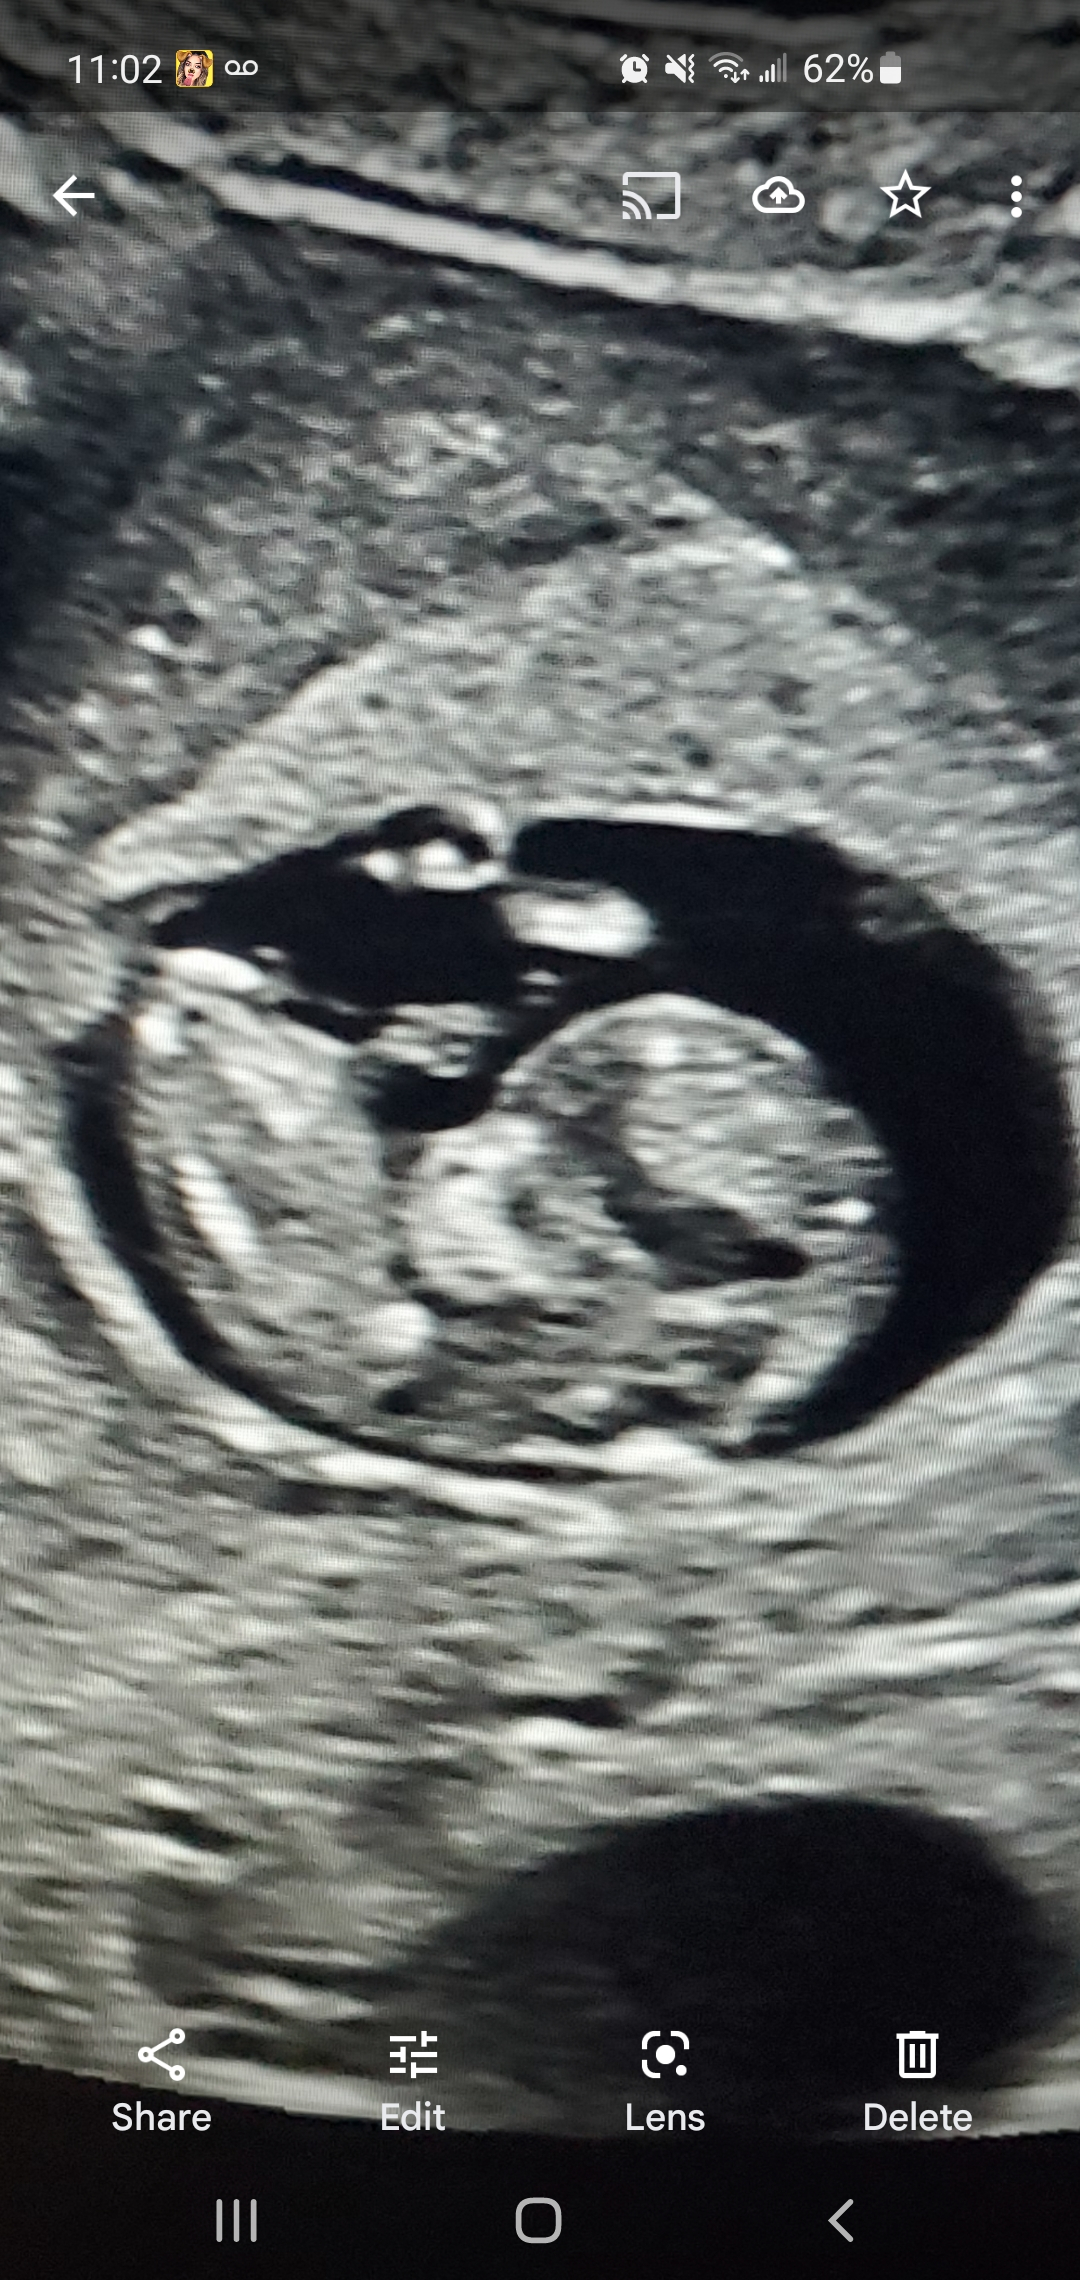

12 weeks 1 day, hr is 163, any guesses???

It’s too early to tell, that’s a profile shot, and no one on here is an ultrasound tech and will be able to give you a better answer than the person who administered it.